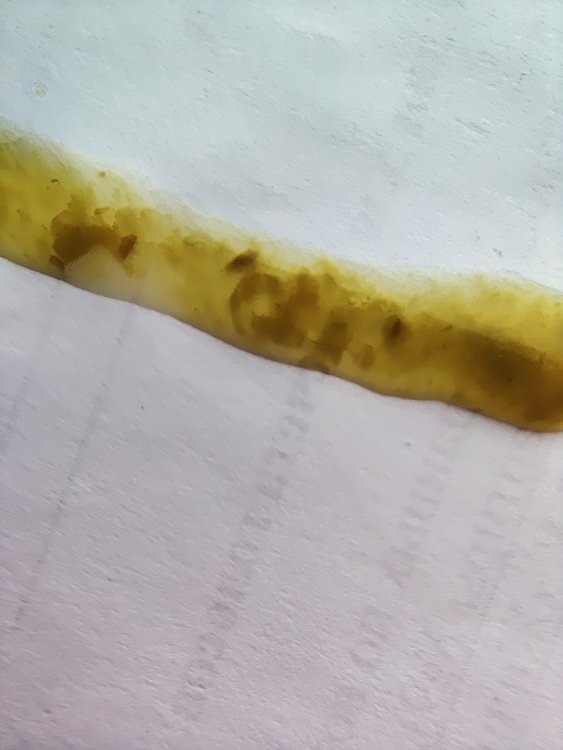

немного размазался но структура сохранена. в основном было такое + вокруг лужицы как на след фото. вот сейчас много такого. сами каки вот такие до этого было чуть более оформленное. сейчас ухудшаться стало. сегодня срыгивали кашу из зоба. вес на данный момент 168 вот на последних фото свежак. в основном такое было. кормлю еще раз распаренной пшеницей. в клюв где-то по 4-8 кубиков за кормление из вот такого устройства кормить стараюсь так чтобы вес поддерживался и чуть сверху еще пару грам

у голубя со вчерашнего дня помет стал насыщенного темно-зеленого цвета, хоть он и ест сам, но почти от всего отказывается кроме льна и семечек, поэтому начали его докармливать кашей домашней (перемолотые: горох, перловка, чечевица) сегодня утром обратила внимание, что сильно пахнет от помета (за ночь). запах кислый, похож на запах творога или кефира. каша за ночь из зоба ушла. к лечению: метронидазол (инфуз) 1.4 х 2р/д; викасол 0.1 х 1р/д и нистатин 1/4 2р/д. Добавила сегодня гепатовет 0.3мл (вечером столько же дам) будет 0.3 х 2р/д фото помета за ночь, который пахнет приложила. подскажите, пожалуйста, кандидоз развивается? нистатин не справляет? или может что-то другое развиваться на фоне приема метронидазола? Восоквицы стали светлее? Чихи по-прежнему есть, но не такие частые. Наросты в горле (в видимой части) остаются, маленькие белые, сфоткать не получается. Самый тревожный сигнал — это помет и то, что голубь ничего не ест. Когда он только прилетел, он хотел есть, просто у него не получалось. Сейчас совсем не ест. Только если положить семечку — ее тут же увидит и съест. Почему так? У него сильная боль в горле? Получается, мы уже неделю на лечении, но наросты полностью не исчезли. Просо он тоже отказывается есть. Продолжать кормить кашей? Если да, то что молоть, учитывая такой помет? Кашу начала давать только вчера -